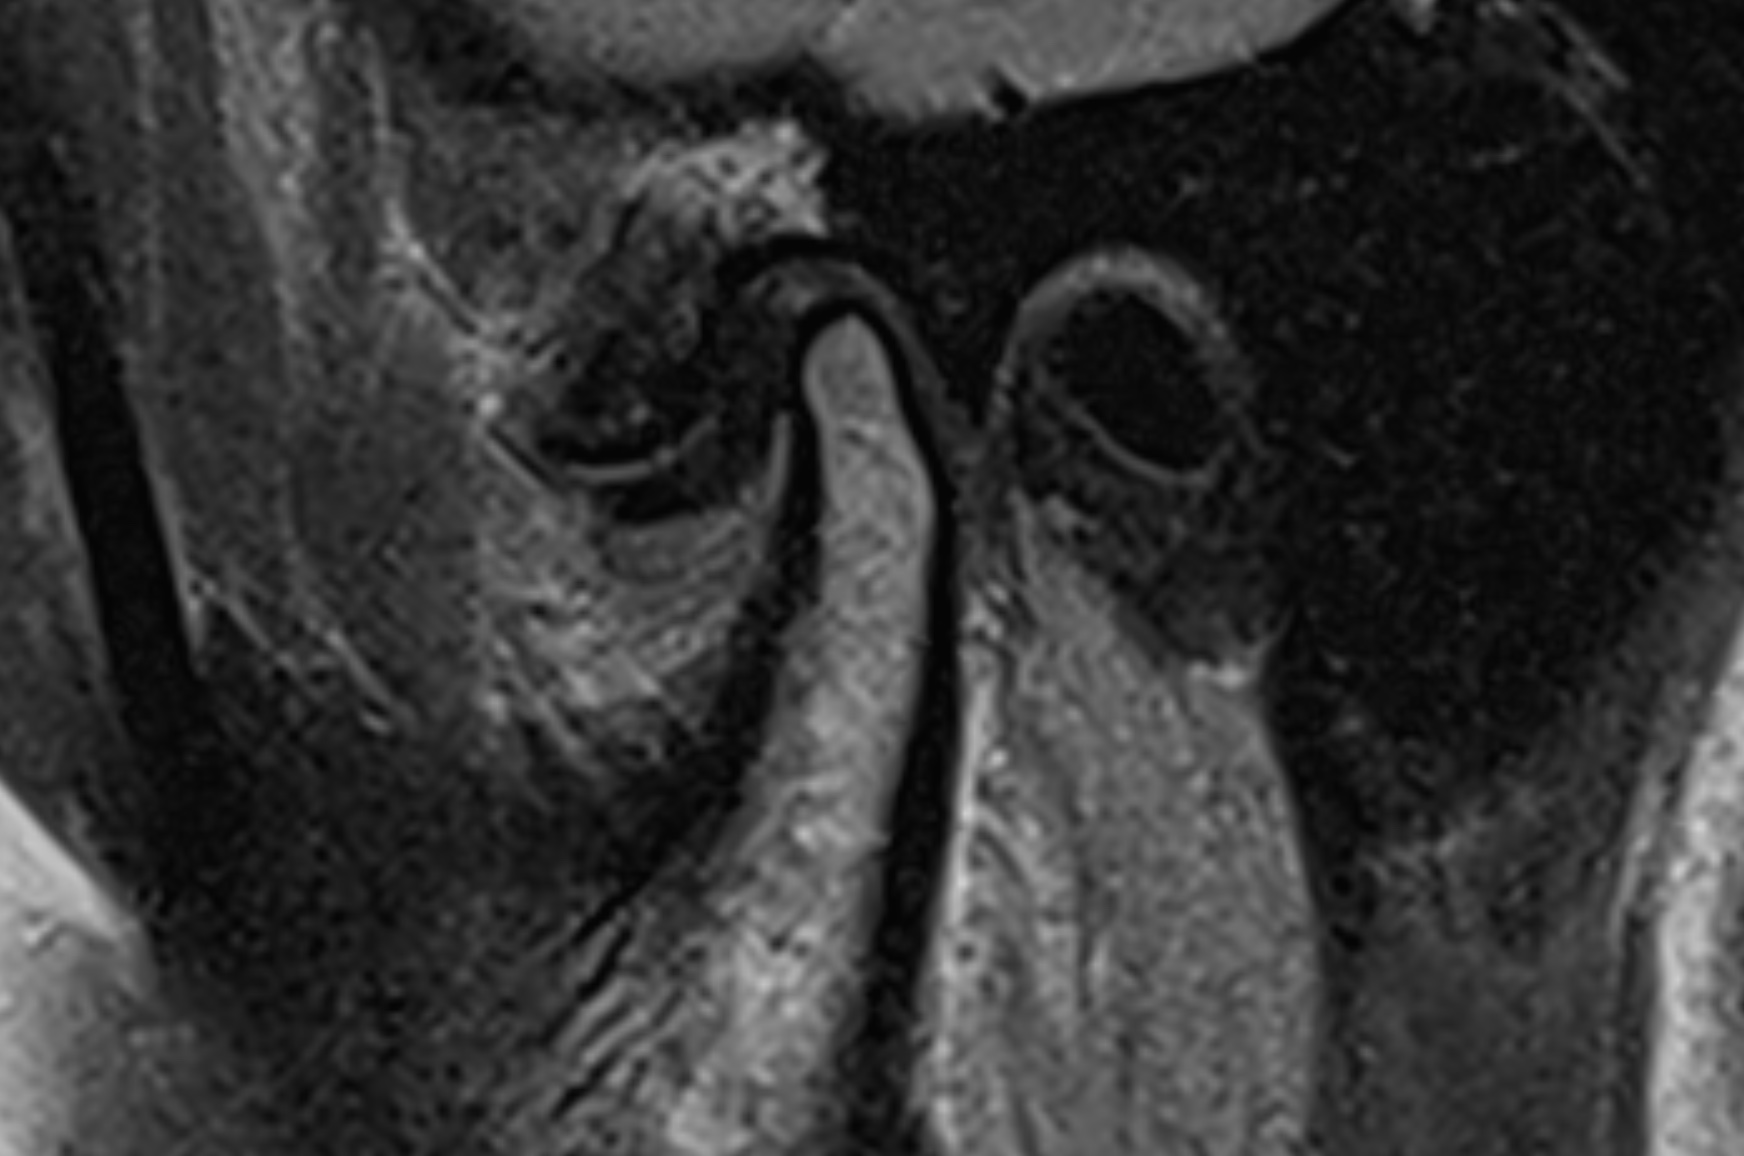

Leddskiven

Leddskiven er en liten støtdemper mellom leddflatene.

På MR kan vi se om den ligger på riktig plass, har forskjøvet seg, eller fått endret form.

Ved tydelig forskyvning kan skiven hindre normal bevegelse, og det kan forklare at kjeven låser seg eller lager klikkelyd.

Bevegelsen av kjeven

MR tas som regel både med lukket og åpen munn.

Da kan vi se hvordan kjeveleddet beveger seg – om skiven følger med som den skal, og om leddhodet har normal bevegelse.